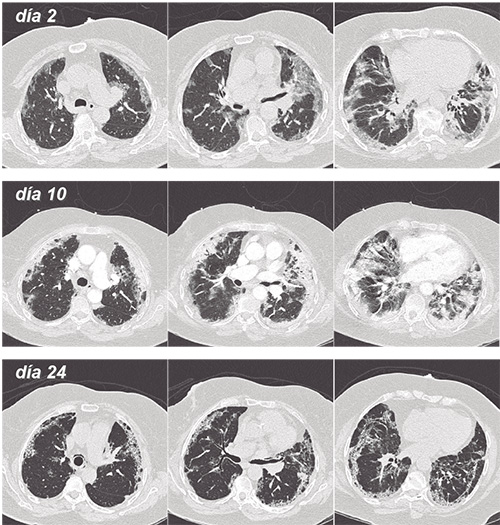

Algunos detractores de esta técnica sugieren que sólo retrasa la conexión al ventilador, favorece el daño pulmonar autoinducido por el paciente o P-SILI, y pudiera llevar a ventilar pacientes con pulmones más dañados, empeorando su pronóstico. Nuestra hipótesis es que la neumonía asociada al SARS-CoV-2, al no tener una terapia específica, sigue su curso –lento, a veces muy lento- independiente de la terapia ventilatoria (Figura).

La tomografía computarizada de pacientes con Covid-19 (Figura), junto con biopsias y autopsias sugiere que la mayoría de estos pacientes tiene una neumonía organizada secundaria (OP) o su variante histológica, neumonía fibrinosa aguda y neumonía organizada, ambas complicaciones bien conocidas de infecciones virales (5).